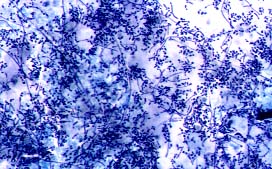

En las Mucormicosis y micosis producidas por especies relacionadas, los agentes causales más frecuentes son: Mucor, Rhizopus y Absidia (Mucorales Zigomicetos). Las especies de Rhizopus son los agentes causantes de Mucormicosis aislados con mayor frecuencia. En general, el hongo ingresa en el organismo a través del tracto respiratorio. Las manifestaciones pueden dividirse arbitrariamente en, al menos, seis entidades, según el órgano afectado: 1) Rinocerebral, 2) Pulmonar, 3) Cutánea, 4) Gastrointestinal, 5) Del sistema nervioso central, 6) Diversas. La 1ª es la que con mayor frecuencia se encuentra en pacientes diabéticos; la pulmonar suele presentarse más en pacientes con aplasia medular secundaria a agentes quimioterápicos; las otras formas son más esporádicas; recientemente se han descrito casos agrupados en algunos hospitales y cuya infección fué debida a la contaminación fúngica de los depresores de lengua (9). En el tejido, muestran estos hongos unas hifas anchas, de 5 a 50 micras (Fig.17), con frecuencia torcidas y no uniformes, sin tabiques, aunque sus invaginaciones los pueden simular; invaden con frecuencia las paredes vasculares y los tejidos adyacentes (Fig.18). Las conidias de los Mucorales no deben tampoco ser confundidas con Nematodes, huevos, ni con otros microorganismos (10).

17.JPG (21699 bytes)

Fig.17

18p.jpg (28017 bytes)

Fig.18